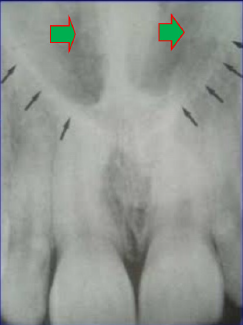

2. What is the anatomical structure indicated by arrow in this radiograph?